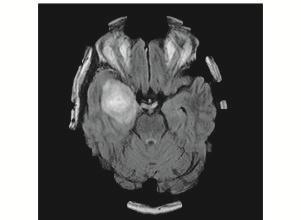

(a)Glioma(b)Pituitary(c)Meningioma(d)Normal

Fig.4. Sampleofimagesfromeachclassofbraintumours generatedfromtheMRI.